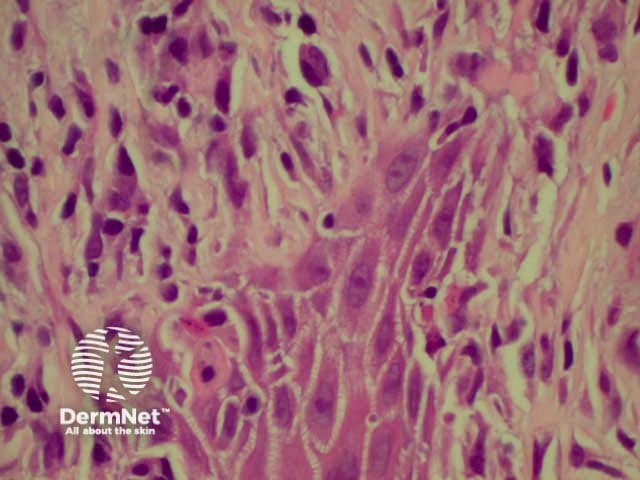

Lichen planus is the idiopathic version of a group of lichenoid disorders characterised by scaling papules or plaques. Link to a clinical description of lichen planus.

The histological features of lichen planus are:

The majority of lymphocytes in the often dense infiltrate are memory cells, identified using histochemistry by positive CD8 and CD45 RO markers.

Direct immunofluorescence nearly always reveals fibrinogen within the colloid bodies. Occasionally IgM and complement are also detected. The immunofluorescence pattern is not diagnostic as the same reactants can also be seen in systemic lupus erythematosus and erythema multiforme.

Lichen planus Lichen planus Lichen planus Lichen planus Lichen planus Lichenoid inflammation